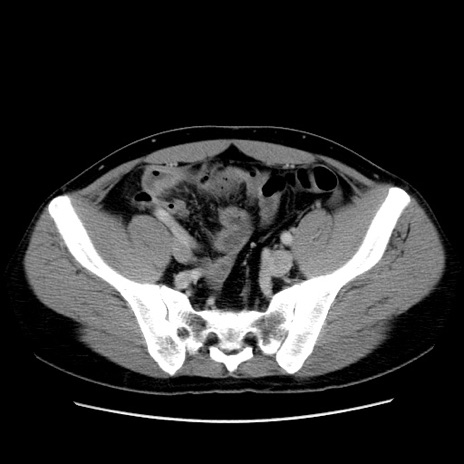

症例4(横断像)

【症例】30歳代男性

【主訴】腹痛、嘔吐

【現病歴】昨晩から突然の腹痛あり、その後嘔吐、軟便も出現。腹痛が改善しないため救急搬送となる。2日前にしめ鯖の食事歴あり。

【身体所見】意識清明、苦悶様、BP 135/90mmHg、BT 35.7℃、腹部:平坦、やや硬、心窩部〜臍部に自発痛、圧痛あり、筋性防御+、反跳痛-

【データ】WBC 8100、CRP 0.57